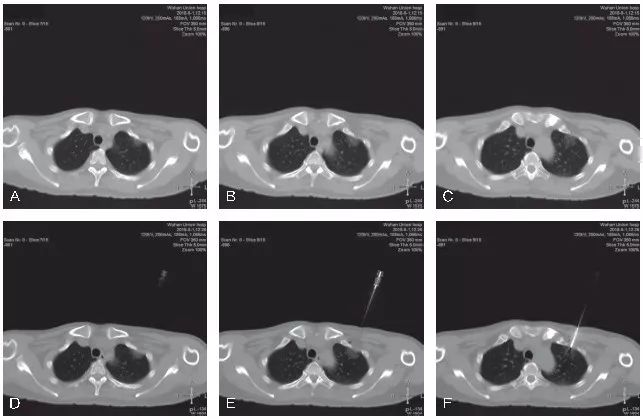

图5-4 展示了1例mGGO的CT 引导下经皮穿刺活检

A~C. 显示患者右肺下叶后基底段mGGO,实性成分处可见胸膜牵拉,选取俯卧位进行穿刺活检;D~F. 显示穿刺活检的实时CT影像,可见同轴穿刺针前端位于mGGO的实性成分处;G~L. 显示活检完成后,拔除同轴穿刺针,再次进行CT扫描,未见明显气胸及肺内出血征象。病理结果示:(右肺)肺泡腔扩张伴肺泡间隔炎性细胞浸润及策划细胞聚集,局灶浆细胞聚集,未见明确肿瘤性病变,请结合临床。